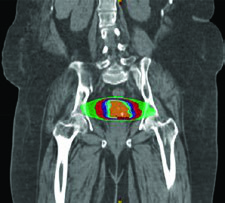

IMRT com Preservação de Medula Óssea

A IMRT pode ser empregada especificamente para preservar medula óssea em pacientes submetidas a RT pélvica, e essa estratégia demonstrou reduzir toxicidade hematológica de forma significativa. Quem trabalha com quimiorradiação concomitante sabe que citopenias prolongadas atrasam ciclos, comprometem dose-intensidade e ocasionalmente levam à hospitalização. Preservar medula ativa é uma resposta concreta a esse problema.

Diversas abordagens foram implementadas e validadas clinicamente:

IG-IMRT baseada em PET/CT envolve contornar os ossos pélvicos e definir medula ativa como regiões com SUV acima do SUV médio intraósseo, aplicando então restrições de dose à medula. As restrições publicadas, baseadas em modelagem NTCP, seguem a seguinte hierarquia:

Quando PET/CT não está disponível, duas alternativas funcionam bem. Uma abordagem baseada em atlas é viável e reprodutível entre centros. A outra opção delimita medula óssea como as regiões de baixa densidade dentro dos ossos no CT de simulação, aplicando as mesmas restrições de dose. Ambas reduzem toxicidade hematológica de forma mensurável, mesmo sem a informação funcional do PET.

Essa estratégia é particularmente relevante para quem trata câncer cervical com quimiorradiação concomitante. A redução de citopenias permite manter a intensidade de dose da cisplatina semanal, o que tem impacto direto no controle tumoral. Detalhes sobre o delineamento dos volumes pélvicos podem ser encontrados nos artigos sobre radioterapia definitiva em ginecologia e tratamento pós-operatório ginecológico.